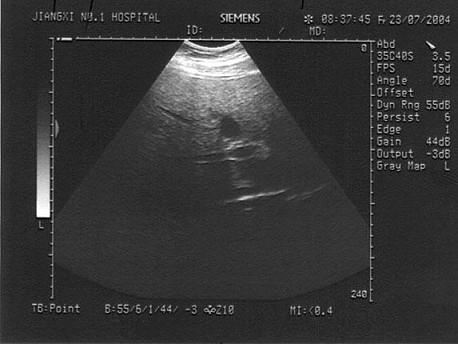

男,19岁。上腹部不适,肥胖。结合超声声像图,诊断为?(?)A.肝癌B.肝硬化C.脂肪肝D.肝炎E.肝豆状核变性

问题 男,19岁。上腹部不适,肥胖。结合超声声像图,诊断为?(?)

选项 A.肝癌 B.肝硬化 C.脂肪肝 D.肝炎 E.肝豆状核变性

答案 C